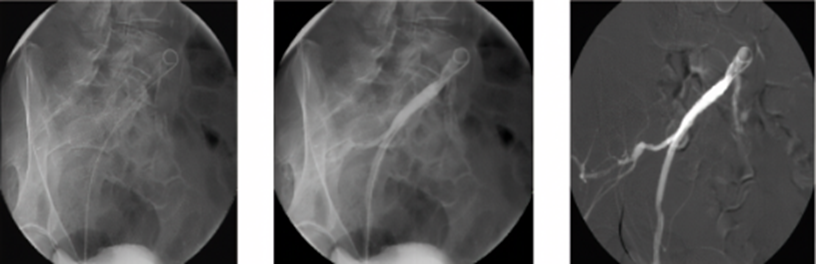

5、数字减影血管造影(DSA DSA被认为是诊断颈动脉疾病的金标准和评价颈动脉狭窄及闭塞的最佳方法。但对血管壁 的 病 变 显 示欠佳,对斑块大小及形态、成分及易损性很难评估。同时该检查有创,容易诱发斑块脱落、血管壁损伤、夹层动脉瘤、动脉瘤、穿刺部位血肿等医源性损伤,在实行有创介入治疗时可考虑,不作为一线检查手段。

图片